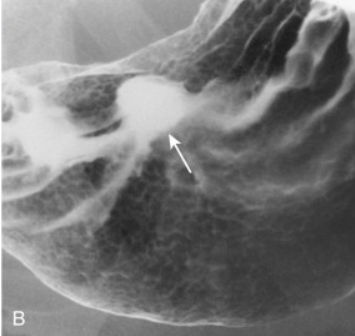

This is a double contrast examination. What is it showing?

A peptic ulcer that is on the posterior wall of the antrum